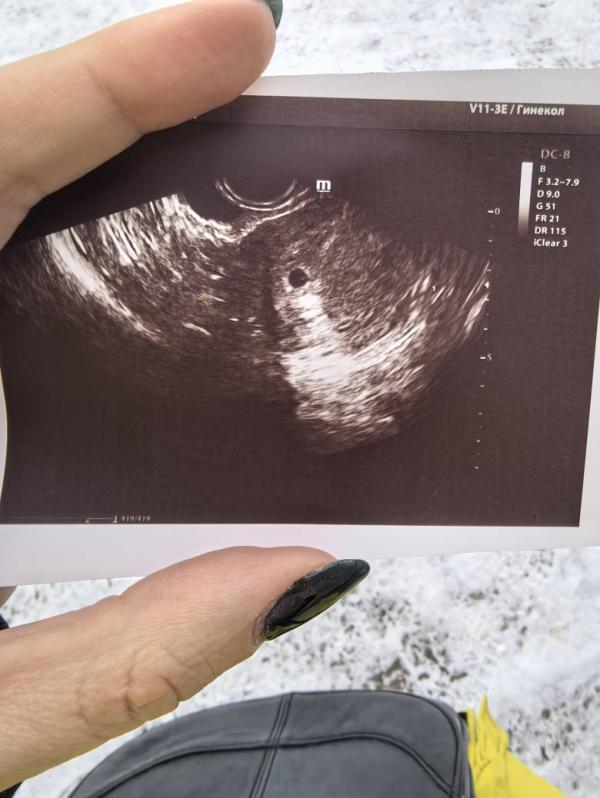

12 января тест показал жирненькую вторую полосочку, 14 января была на первом УЗИ для подтверждения. Всё у нас хорошо, беременность маточная. По узи срок 4 полных недели. 🥳

Повторно иду на узи 24 января, будем слушать сердечко. 💞